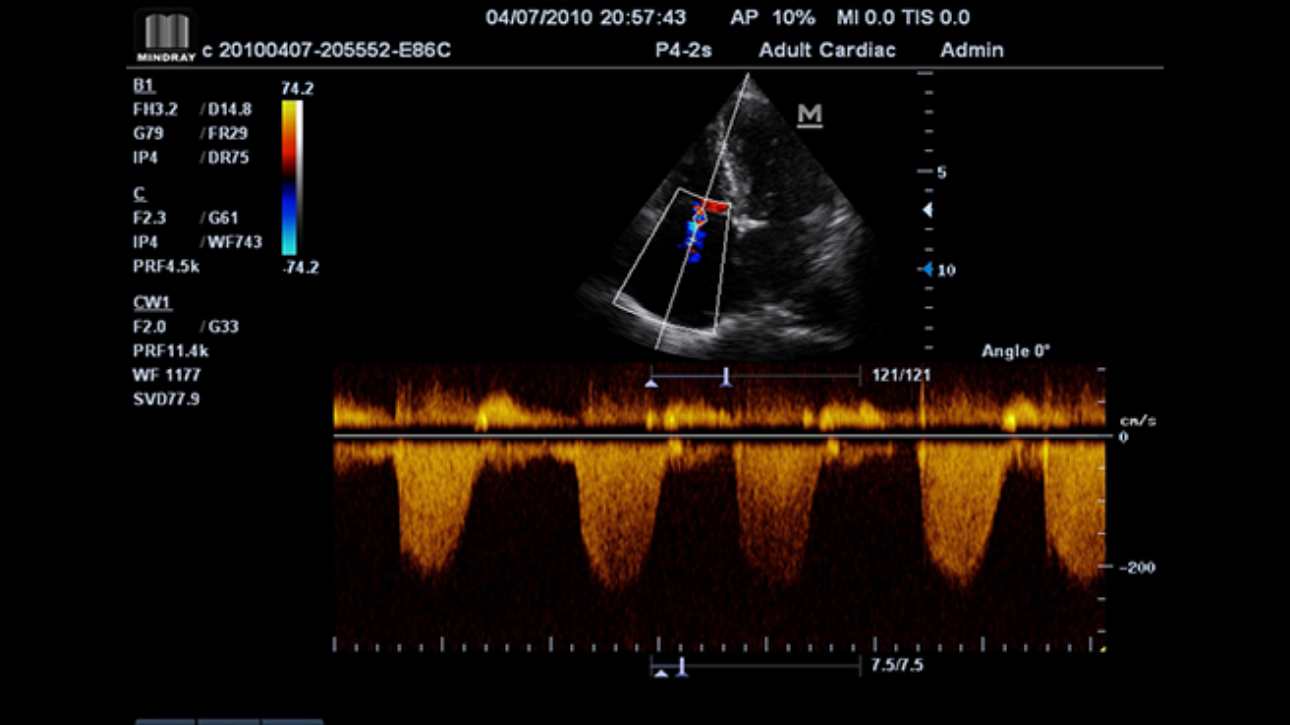

Award winning portable hand-carried color Doppler, M7 Premium is a High level system with excellent performance. Equipped with dedicated cardiac package and easy-to-use workflow software, M7 Premium offers an ideal packaged solution to address the needs of cardiologists.

Performance

Gain accurate measurement of the myocardial function in response to external stress or pharmacy.

Gain precise anatomical observation by freely placing sample lines at any angle. Attain better images through simultaneous display of up to 3 sample lines.

Tissue Doppler Imaging allows you to quantitatively evaluate local myocardial movement and function, providing complete TDI modes for faster and direct diagnoses.

Accurately evaluate myocardial motion at different phases, and simultaneously determine myocardial synchronization. High frame-rate providing you with accurate results.